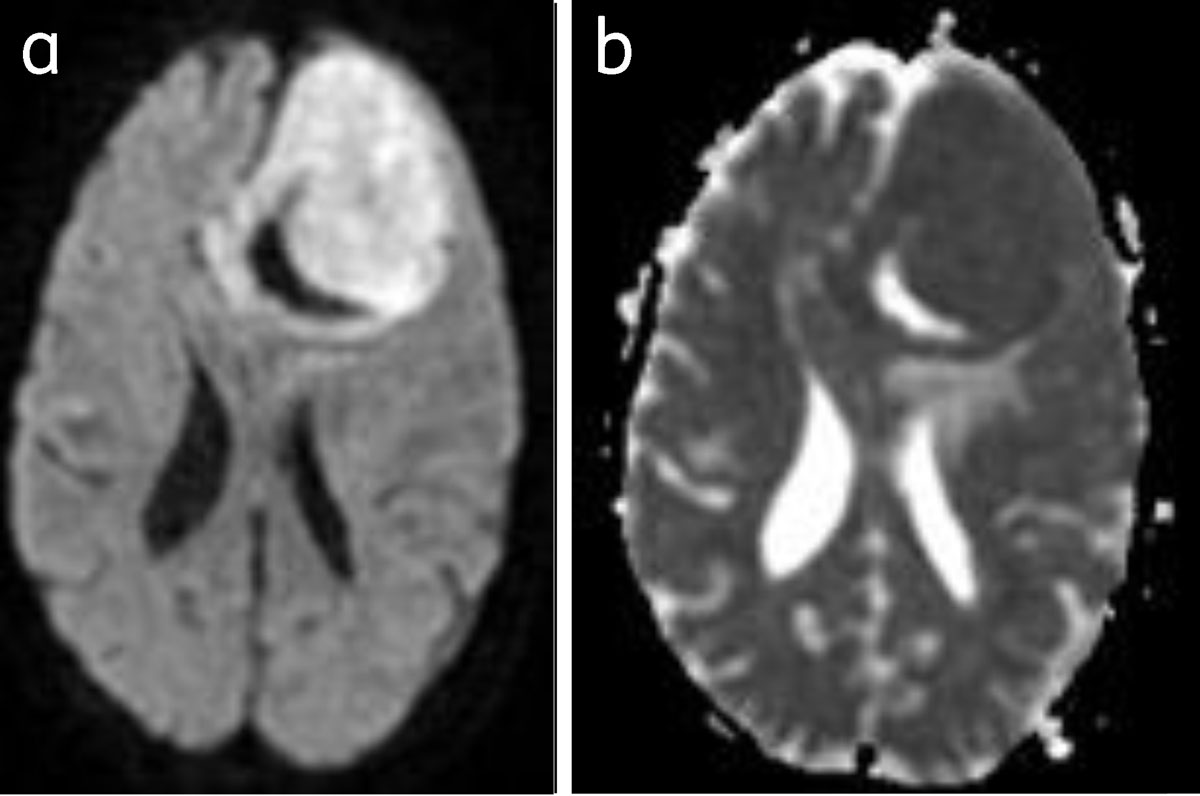

The role of diffusion weighted imaging for grading meningiomas is inconclusive [9] (Figure 12).

Figure 12

Meningioma with restriction of diffusion: Bright on DWI (a) and dark on ADC (b).